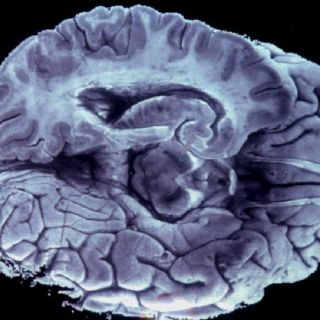

WASHINGTON, ESTADOS UNIDOS (30/ENE/2012).- La parte del cerebro humano que procesa el habla se encuentra localizada en una sección diferente a la que se creía, de acuerdo con un estudio estadounidense publicado este lunes, por lo que los científicos señalaron la necesidad de actualizar los textos médicos.

Durante mucho tiempo, se creyó que el área de Wernicke, que lleva el nombre del neurólogo alemán que la definió a finales de los años 1,800, se localizaba en la parte posterior de la corteza cerebral, detrás de la corteza auditiva, que procesa los sonidos.

Pero un estudio científico del Centro Médico de la Universidad de Georgetown, en Washington, que tomó en cuenta más de 100 resonancias magnéticas, mostró que el área de Wernicke está tres centímetros más cerca de la parte frontal del cerebro y que se encuentra delante de la corteza auditiva, y no detrás como se creía.

Un análisis de las imágenes cerebrales del estudio arrojó la nueva localización del el área de Wernicke, dando una nueva perspectiva para tratar a los pacientes que sufren de daño cerebral o embolia.